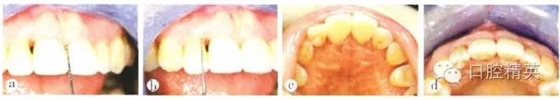

患者全身狀況良好,無過敏史及長期服用藥物史,否認吸煙史??谇粰z查:口腔衛(wèi)生尚好,菌斑、軟垢少,牙石+~++;個別牙齦輕度紅腫,出血指數(shù)(bleeding index,BI)為1~3,654 456牙齦退縮明顯;全口探診深度(probe depth,PD)3~5 mm,附著喪失,根分叉病變(furcation involvement,F(xiàn)I)個別1~2度,無松動;7缺失,1先天缺失,雙側(cè)第一磨牙近中關(guān)系。高位笑線,前牙I度深覆蓋,211牙冠呈尖圓形,牙齦退縮約1.3 mm,齦乳頭缺失,屬Miller III類.鄰面根頸部可見“黑三角”(圖1)。

a上前牙區(qū)正面觀;b上前牙區(qū)牙合面觀;c上前牙區(qū)腭側(cè)觀;d患者微笑像,可見上前牙區(qū)存在“黑三角”;e上前牙區(qū)側(cè)面觀

圖1初診時上前牙區(qū)口內(nèi)像及微笑像